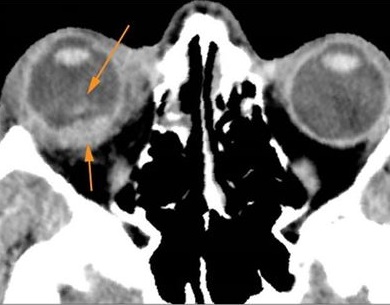

Possible facial, mandibular, orbital, and/or skull fractures, due to craniofacial trauma.Exam

Non-contrast CT of the maxillofacial region was obtained with 0.5-1.0 mm thick sections in the axial plane and reformatted 3D and/or in the coronal and sagittal planes and viewed interactively in 3 dimensions at the computer workstation.